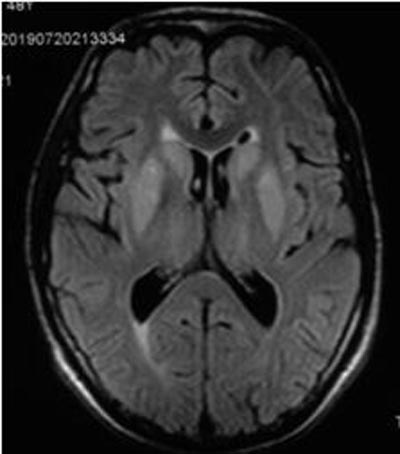

患者男性,42岁,因“嗜睡1月余,阵发性面部抽搐1天”入院。患者既往在当地因“食管癌”行手术及放化疗,自诉已恢复良好。患者MR片显示双侧基底节区对称性T2WI、FLAIR系列高信号,DWI序列提示弥散轻度受限。入院当天离子五项显示钾离子、钠离子、氯离子、镁离子均降低,其中钠离子为131.4mmol/L。遂询问患者家属相关病史,患者于1月前出现嗜睡,于当地医院对症治疗(补充电解质)稍好转,随后出现阵发性面部抽搐,为进一步治疗转至我院。综合病史及实验室检查,高度提示脑桥外髓鞘溶解(extrapontine myelinolysis , EPM)。

CPM 常累及脑桥基底部,呈现对称性类似"蝙蝠样"病灶,其中髓鞘溶解,而神经元突相对完好,从中缝向两侧发展。而EPM多累及基底节、皮质、小脑等脑桥外结构[2]。发病初期CT检查对本病可无异常发现。故磁共振成像 (MRI) 对诊断ODS 起到重要作用,尤其是MR弥散加权成像 (diffusion weighted imaging , DWI) 及表观扩散系数 (apparent diffusion coefficient , ADC)使得 ODS 的早期诊断成为可能。

FLAIR